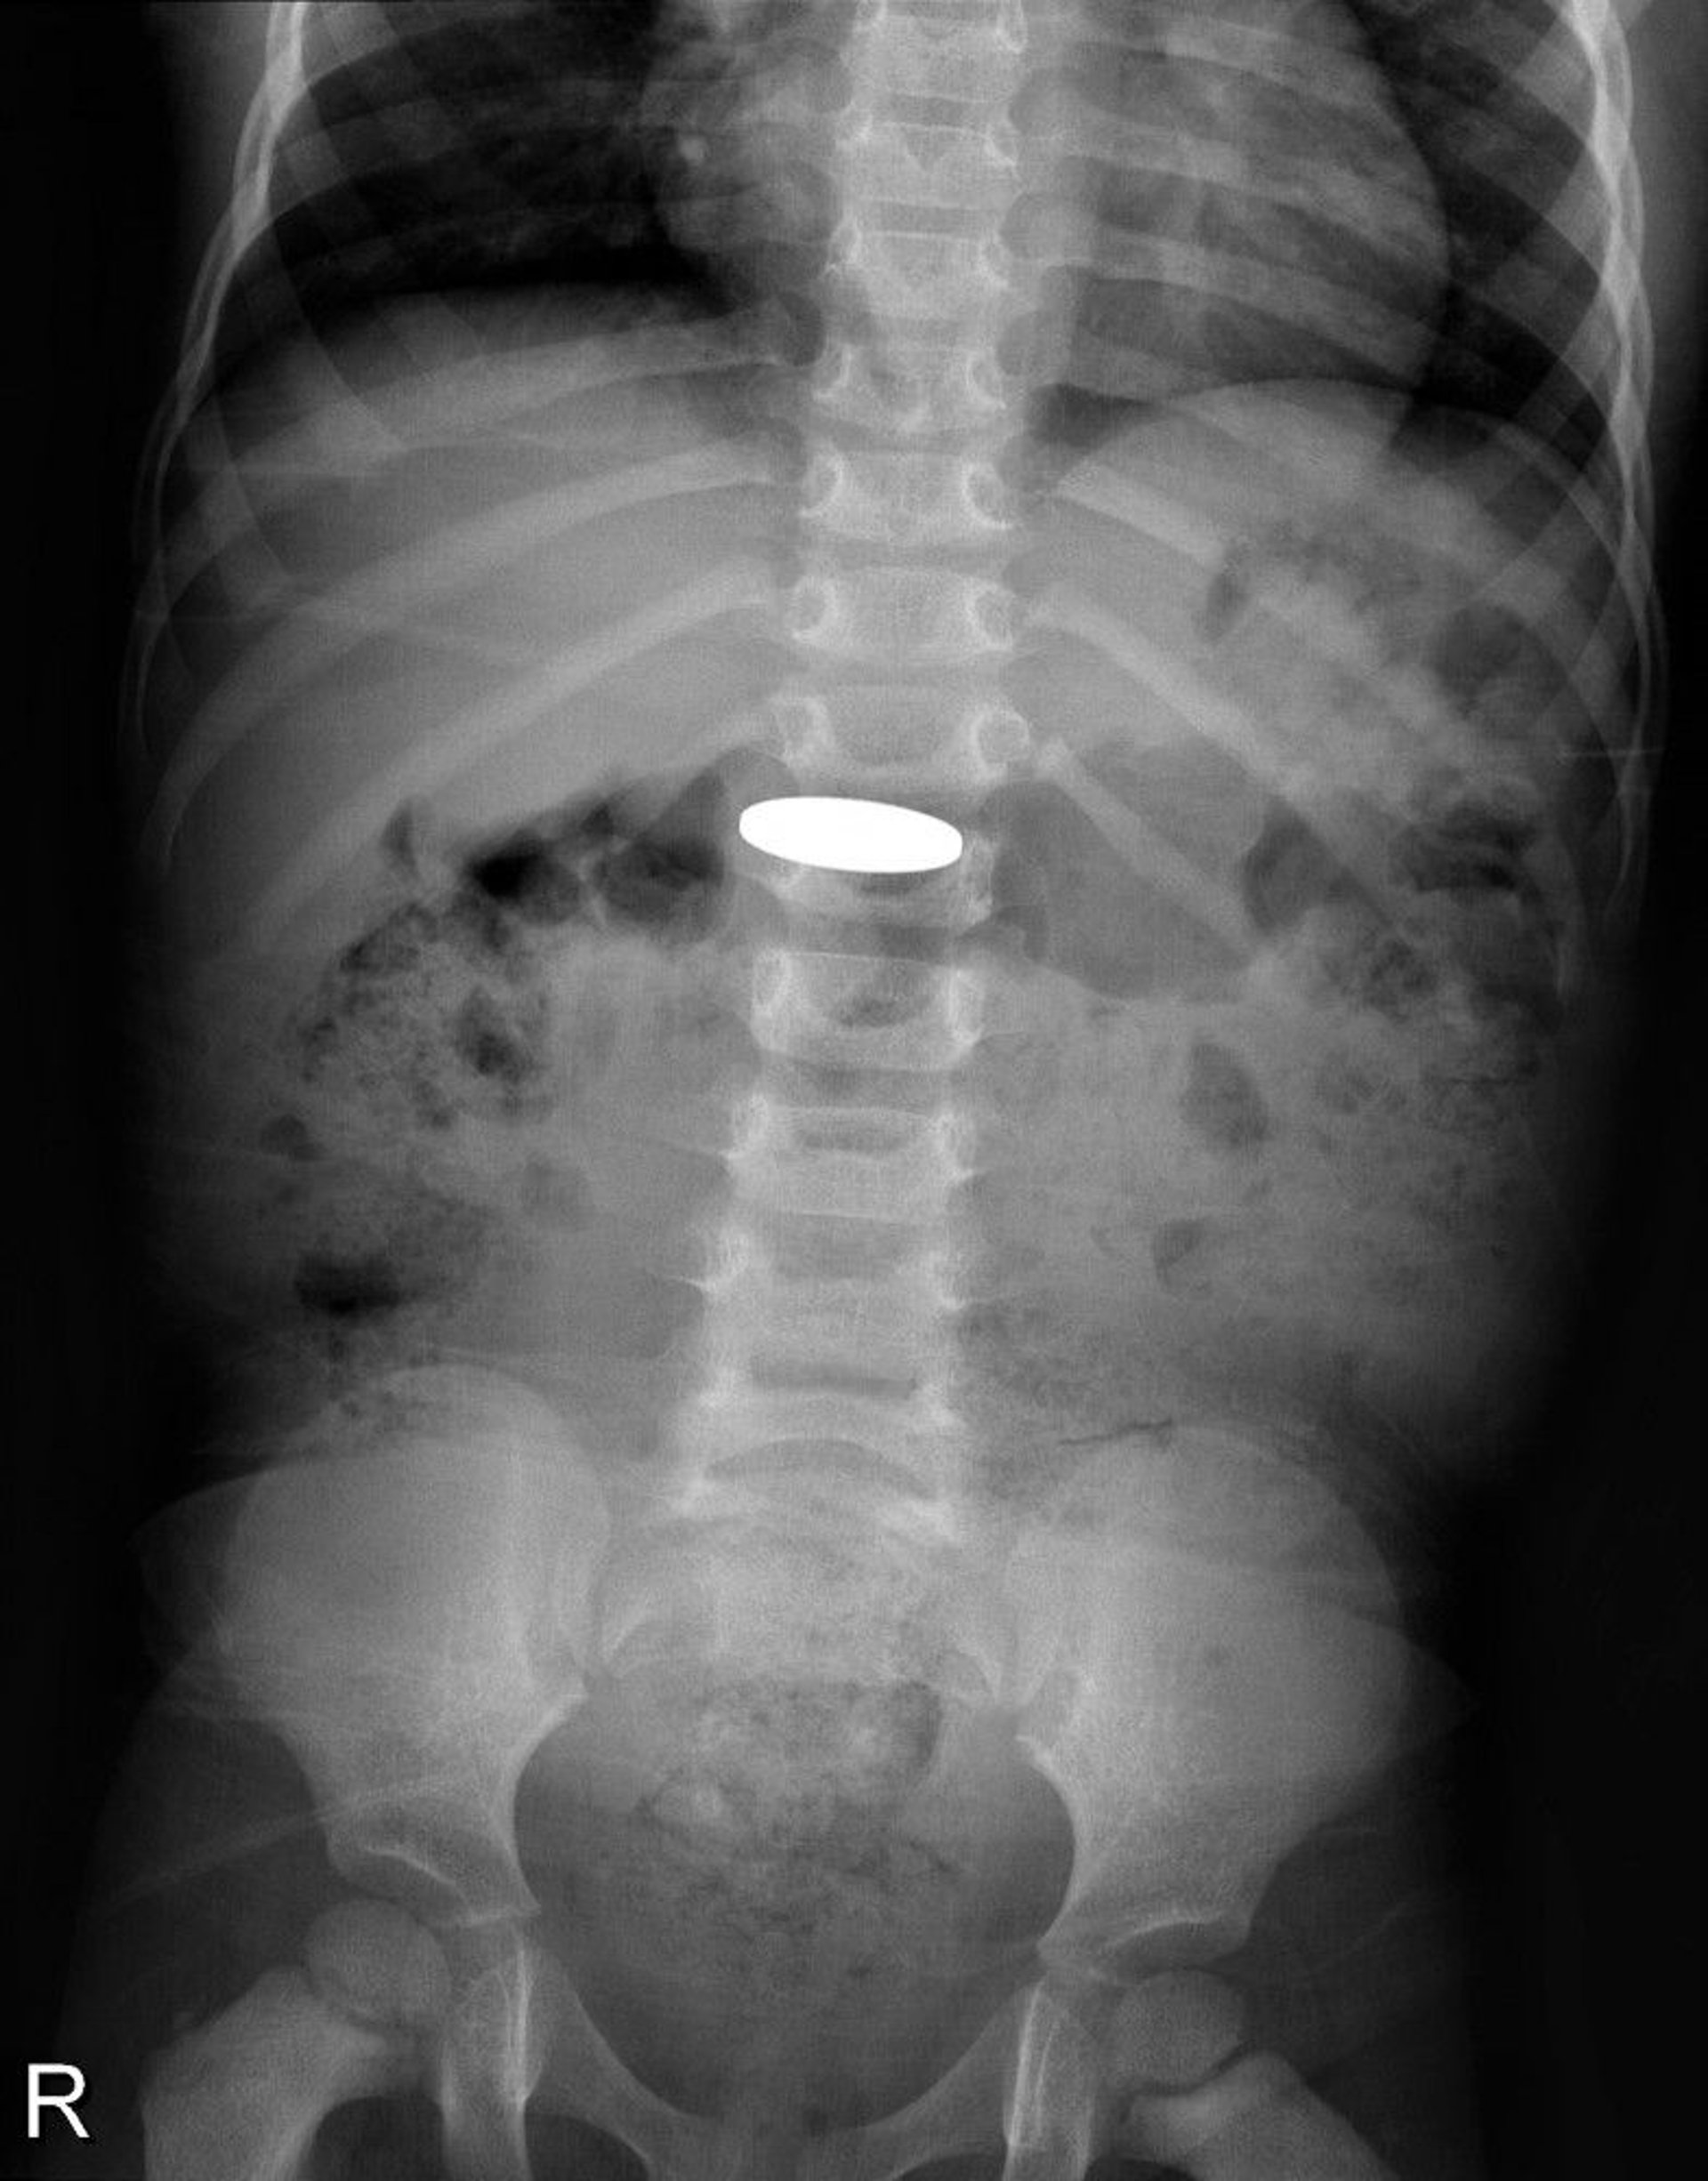

Foreign Body in the Gastrointestinal Tract (Radiograph)

This radiograph shows a coin that was swallowed by a young child.